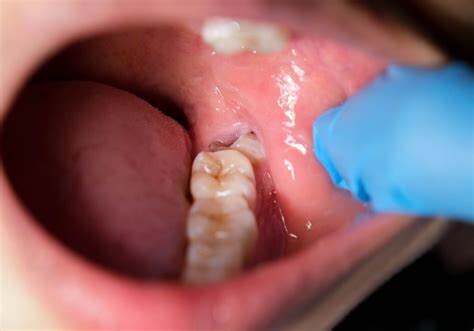

Oral Health Problems

In some cases, jaw pain on one side can indicate underlying oral health problems. Some common issues that cause jaw pain are cavities, an abscessed tooth, gum disease, tooth decay, growth of wisdom teeth, missing or crooked teeth, and clenching or grinding your teeth.